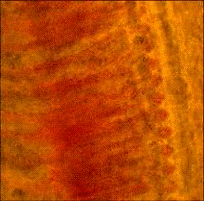

При микроскопическом исследовании на живом

материале и на срезах пораженных жабр карпов были обнаружены образования, не встречающиеся

на жабрах здоровых рыб. В побелевших и отекших концах жаберных лепестков

находили большое количество мелких одноклеточных амебоидов, которые двигались

(рис. 1). Они образовывали пальцевидные или сосочковидные псевоподии, которые

отходили от широких лопастей (при изучении живых амеб). При исследовании с

помощью сканирующего электронного микроскопа (рис. 2) было видно, что

трофозоиты имели большую длину, чем ширину. Плотная кутикула, размеры тела,

размеры (длина между 13-26 µм, соотношение длины к ширине 1,0-2,4) и другие

морфологические признаки позволяют отнести данный организм к роду Mayorella

сем. Paramoebidae.

Рис. 1. а. Жабры больных карпов: 1 - гиперплазия

жаберного эпителия (х 400); б. Зернистые амебоиды из жаберных лепестков больных

карпов (х 480)

Гистопатологические изменения в жабрах

проявлялись в виде гиперплазии и гипертрофии жаберного эпителия.

Рис. 2. Mayorella

sp. с жабр карпа

(сканирующий электронный микроскоп)